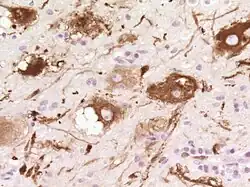

Histologicznie stwierdza się pogrubienie warstwy ziarnistej wewnętrznej kory móżdżku i liczne dysplastyczne neurony (komórki zwojowe) mające pęcherzykowate jądro komórkowe z widocznym jąderkiem[6].